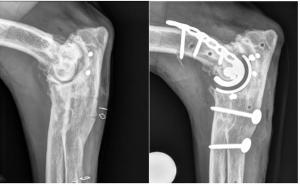

Guiot, a renowned orthopedic surgeon, graduated with a veterinary medicine degree from the University of Liege (Belgium) in 2004. Board-certified by the American and European College of Veterinary Surgeons in 2011, he has held prominent positions, including assistant professor of orthopedic surgery at Michigan State University. Since his arrival at ACCESS Specialty Hospital-Los Angeles, he co-developed with Reunan Guillou the first comprehensive total joint replacement center in California, offering surgeries like total elbow, hip, knee, and ankle replacements. The ACCESS Bone and Joint Center, a part of Thrive Pet Healthcare’s community of hospitals, is the only complete orthopedic center for pet joint replacements on the West Coast.